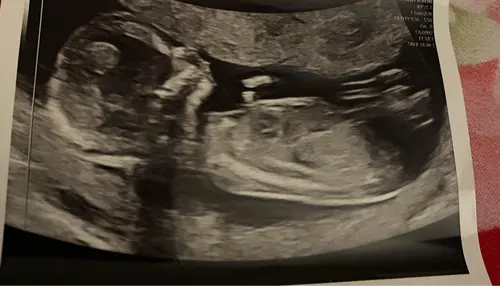

Ik kan t niet heel goed zien, maar ik denk de nub te kunnen zien ook?

Dus m ...

Dat heeft ze bewust verdoezeld want ze was vrij zeker van geslacht maar vertelde het niet omdat het 13 weken echo was, benieuwd